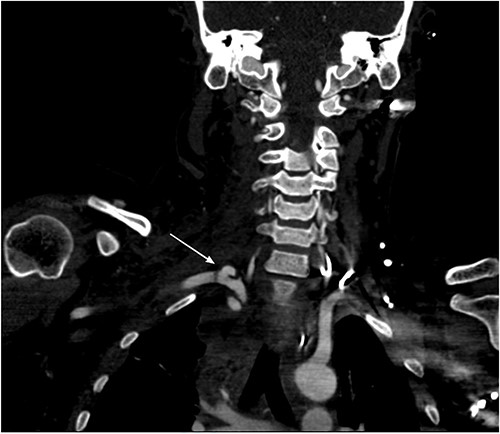

She remained hemodynamically stable; therefore, the patient was transferred to Computed tomography (CT) scan for optimal preoperative planning. Head and neck CT showed right common carotid dissection with a small pseudoaneurysm (Fig. 2). And bullet fragment causing proximal filling defect measuring 1.4 cm long without active extravasation. Surrounding the right common carotid was a hematoma extending to the anterior neck and superior mediastinum. Also, Right subclavian dissection with three pseudoaneurysms (Fig. 3) proximal and distal to the right vertebral artery takeoff, the largest measures 1.1 × 0.8 cm. Multiple scattered metallic fragments were also noted at the subcutaneous tissue of bilateral temporal bones and the occipital area.

Right common carotid intimal flap (upper arrow) and pseudoaneurysm at origin (lower arrow).